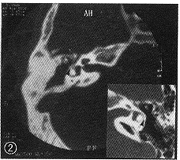

體位和範圍:橫斷面,仰臥位,以聽眶線向上連續掃描至鼓竇蓋;

冠狀面,俯臥位,以冠狀線垂直聽眶線自外耳孔前緣向後連續掃描

掃描基準線:橫斷掃描——聽眶線(仰臥位);冠狀掃描——冠狀線(俯臥位)

層厚和層距::超薄層0.5~2mm;薄層3~5mm。

窗寬和窗位:軟組織窗:L30~50HU,窗寬:W250~300HU

骨窗:窗位L250~500HU,窗寬:W1000~1600HU。